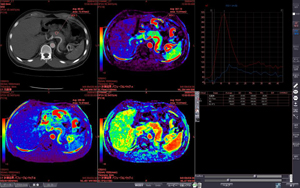

今回ITEMで初めて紹介されるziostation2の最新バージョンでは,従来から定評のある脳血流解析に加え,膵血流など体幹部の解析も可能にした「CT/MR血流解析」,「CTボリューム血流解析」,Dual Energy CT装置のデータを用いて抽出したい物質のCT値の範囲を指定しボリューム情報を分離する「D.E.デコンポジション」,神経線維の走行解析を行い,さらにMRAやCTAともフュージョン可能な「MRトラクトグラフィー」などを新たに搭載しました。より幅広い分野の検査をサポートします。 このほか,次期バージョンで搭載予定のMR心臓検査画像から右心室の機能解析を行う「MR右心機能解析」や 心壁の局所的な壁運動の異常を解析する「MRストレイン解析」なども紹介します。